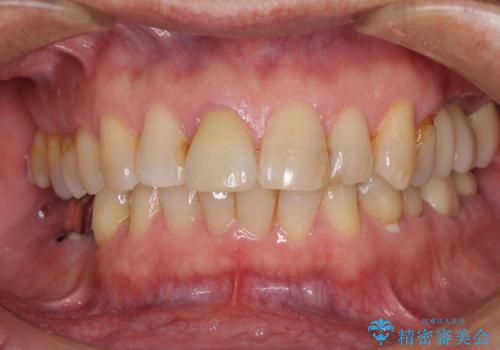

部分矯正を併用した奥歯のインプラント補綴治療

- 奥歯を他院で抜歯した後、インプラント治療を希望とのことで来院された患者様です。

部分矯正期間中はアンカースクリューやフック、ゴムなどが粘膜にあたり、大変な思いをすることになりましたが、そのおかげでインプラント補綴した歯と最後方歯の位置が非常に良好となり、まるでご自身の歯のように咬むことができるようになりました。